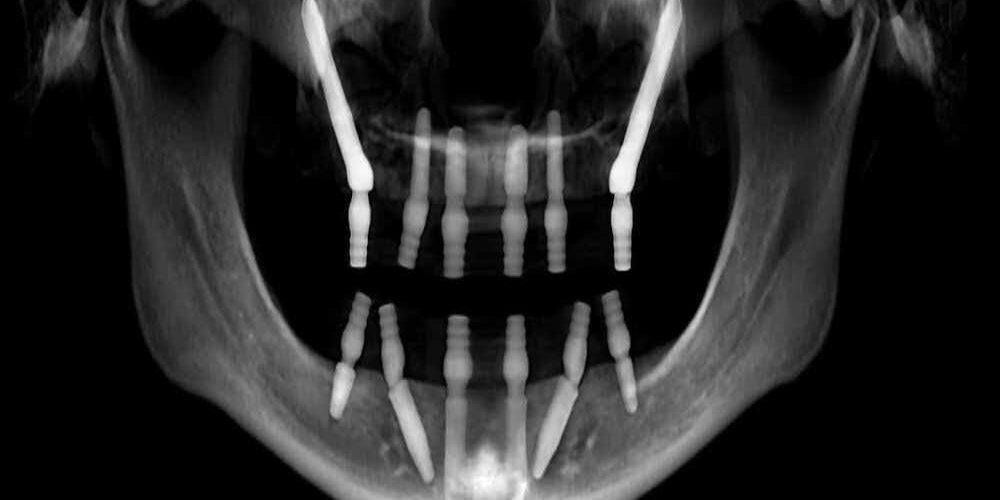

Zygomatic implants

Zygoma implant is one of the best option for replacement of missing teeth in case where there is atrophied maxillary bone with higher success rate. The implants are longer than conventional implants and are to be place in the zygomatic bone which will provide good stability.

The procedure need to be perform under conscious sedation or local anesthesia and no bone grafting procedure is require so no need to wait for 6-8 months for graft maturation and no 2nd surgery require. During the postoperative period there are no excessive discomforts and the greatest advantage is the fast treatment, quick recovery and patient can have the teeth on the same day.

Pterygoid Implants

Pterygoid implant is a favorable option for replacement of missing teeth with deficient or atrophied maxilla. The implants are longer than conventional dental implants and provide good stability.

The procedure is done under local anesthesia but if the patient is too anxious the procedure can be perform under conscious sedation and the implant is place in the back of the upper jaw. The procedure does not affect the daily routine, has fewer post operative complications and discomfort with a success rate of around 95%.

Angled implants

As the name suggest, angled implants are those implants which are angled or inclined in such a way that they avoid the maxillary sinus in atrophied maxilla thereby preventing complications arises due to perforation into the sinus. They also avoid the use of bone graft thereby reducing the treatment time and multiple surgeries. Besides, the teeth can be fixed on the same day.